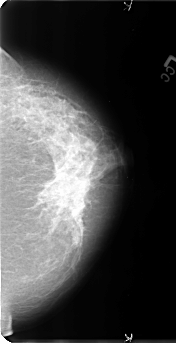

B_3128_1.LEFT_CC

LEFT_CC LINES 4816 PIXELS_PER_LINE 2464 BITS_PER_PIXEL 12 RESOLUTION 50 NON_OVERLAY